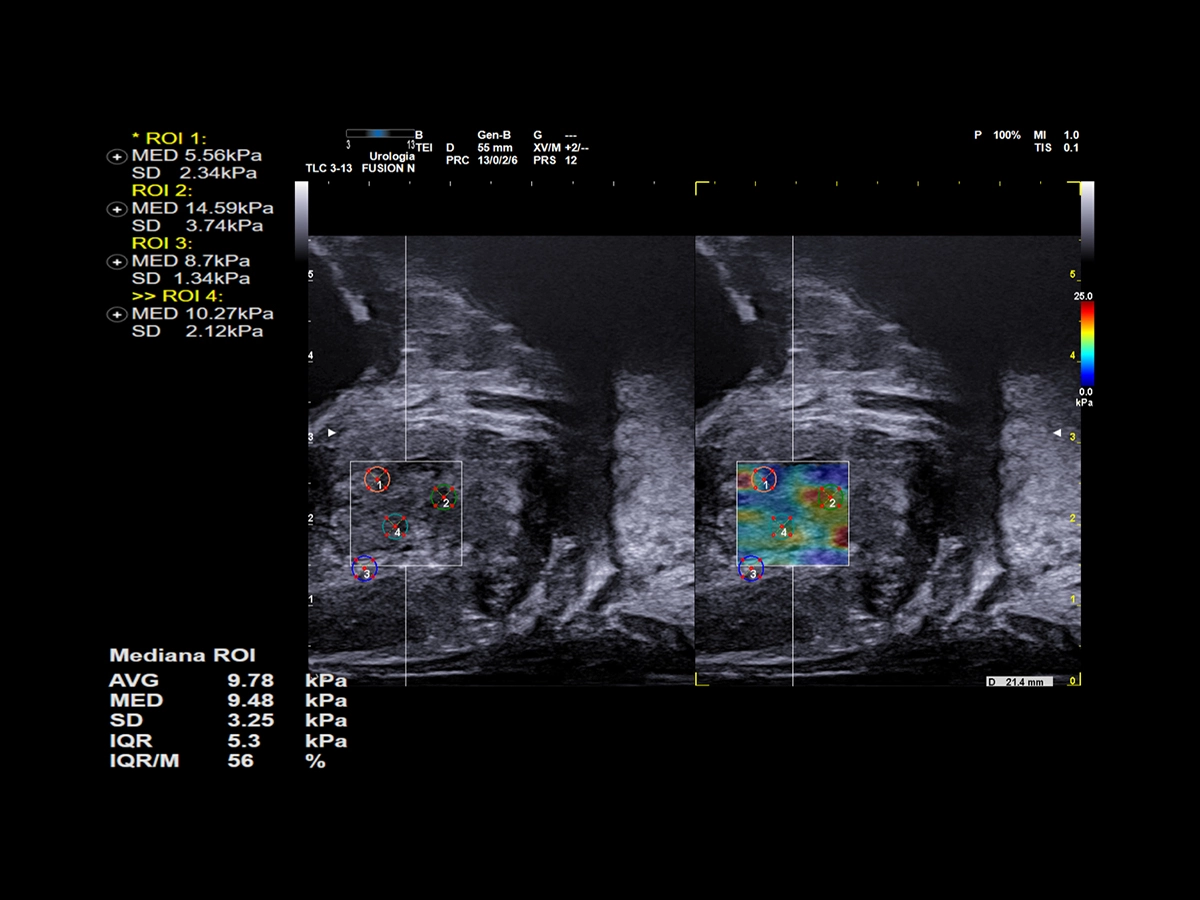

ElaXto and QElaXto 2D are Esaote’s strain and shear wave elastography technologies, which provide information on tissue elasticity by displaying a color-coded map representing prostate stiffness either relatively or quantitatively.

QElaXto 2D on sagittal view in suspected anterior region